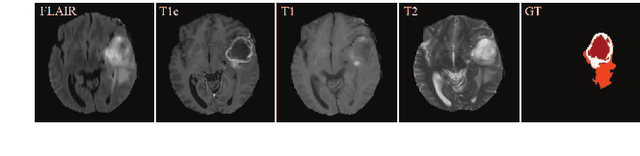

Abstract:In the field of multimodal segmentation, the correlation between different modalities can be considered for improving the segmentation results. Considering the correlation between different MR modalities, in this paper, we propose a multi-modality segmentation network guided by a novel tri-attention fusion. Our network includes N model-independent encoding paths with N image sources, a tri-attention fusion block, a dual-attention fusion block, and a decoding path. The model independent encoding paths can capture modality-specific features from the N modalities. Considering that not all the features extracted from the encoders are useful for segmentation, we propose to use dual attention based fusion to re-weight the features along the modality and space paths, which can suppress less informative features and emphasize the useful ones for each modality at different positions. Since there exists a strong correlation between different modalities, based on the dual attention fusion block, we propose a correlation attention module to form the tri-attention fusion block. In the correlation attention module, a correlation description block is first used to learn the correlation between modalities and then a constraint based on the correlation is used to guide the network to learn the latent correlated features which are more relevant for segmentation. Finally, the obtained fused feature representation is projected by the decoder to obtain the segmentation results. Our experiment results tested on BraTS 2018 dataset for brain tumor segmentation demonstrate the effectiveness of our proposed method.

Abstract:In the field of multimodal segmentation, the correlation between different modalities can be considered for improving the segmentation results. In this paper, we propose a multi-modality segmentation network with a correlation constraint. Our network includes N model-independent encoding paths with N image sources, a correlation constraint block, a feature fusion block, and a decoding path. The model independent encoding path can capture modality-specific features from the N modalities. Since there exists a strong correlation between different modalities, we first propose a linear correlation block to learn the correlation between modalities, then a loss function is used to guide the network to learn the correlated features based on the linear correlation block. This block forces the network to learn the latent correlated features which are more relevant for segmentation. Considering that not all the features extracted from the encoders are useful for segmentation, we propose to use dual attention based fusion block to recalibrate the features along the modality and spatial paths, which can suppress less informative features and emphasize the useful ones. The fused feature representation is finally projected by the decoder to obtain the segmentation result. Our experiment results tested on BraTS-2018 dataset for brain tumor segmentation demonstrate the effectiveness of our proposed method.